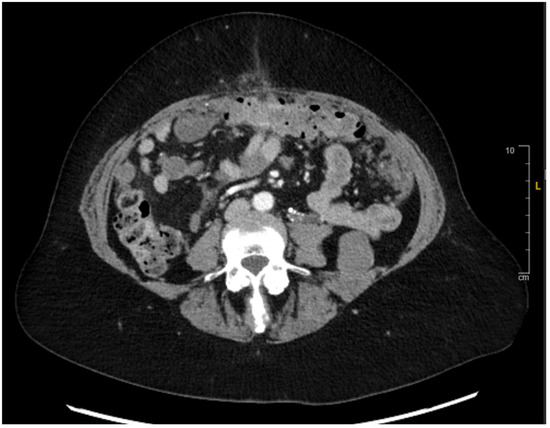

2. Case Presentation